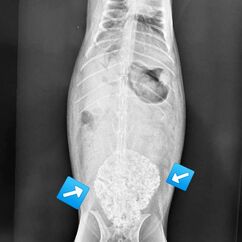

Zu jeder Impfung gehört eine Allgemeinuntersuchung. Mit 6 Jahren gehört Lotti zu den älteren Kaninchen und gerade bei Weibchen kommen dann Gebärmutterprobleme häufig vor. Bei der Allgemeinuntersuchung fiel mir dann eine etwa faustgroß derbe Umfangsvermehrung auf (so heißt medizinisch erst einmal alles, was nicht da sein sollte). Wir haben geröngt und Blut genommen, nicht, dass da noch eine Überraschung zu Tage tritt und haben schon im Röntgen gesehen, dass da etwas ganz und gar nicht stimmt. Lotti hatte eine kalzifizierte Umfangsvermehrung im Bauch. Das kann jetzt einiges sein, daher hat ein sehr netter Kollege einmal mit dem Ultraschall genauer nachgeschaut und der Verdacht eines Gebärmuttertumors war dann sehr stark. Im Blutbild zeigte sich eine heftige Entzündung, was nicht so ganz zu einem Tumor passt. Lotti wurde mit Schmerzmitteln und einem Antibiotikum abgedeckt und innerhalb einer Woche wurde sie auch zunehmend schmerzhaft, das zeigt sie trotz Schmerzmitteln deutlich. Die Kastration ging einfach und besser, als wir dachten, aber sie war deutlich schwieriger, als eine normale Kastration, denn Tumore haben eine ganz unangenehme Eigenart : Sie werden mit Blut versorgt und es sind meist sehr dicke Blutgefäße. Der Tumor ist 6x4x5cm groß und wiegt knapp 100g (viel bei gerade 1.8kg Gesamtgewicht). Zum Glück dürfen wir den Tumor auch einschicken, es steht einiges im Raum und wir wollen schon wissen, wie es prognostisch aussieht. Das Ergebnis zeigt einen bösartigen Tumor, wie es leider bei den Weibchen häufig vor kommt. Die Ränder sind sauber, an einer Stelle war er leider offen, das haben wir in der OP bereits gesehen.